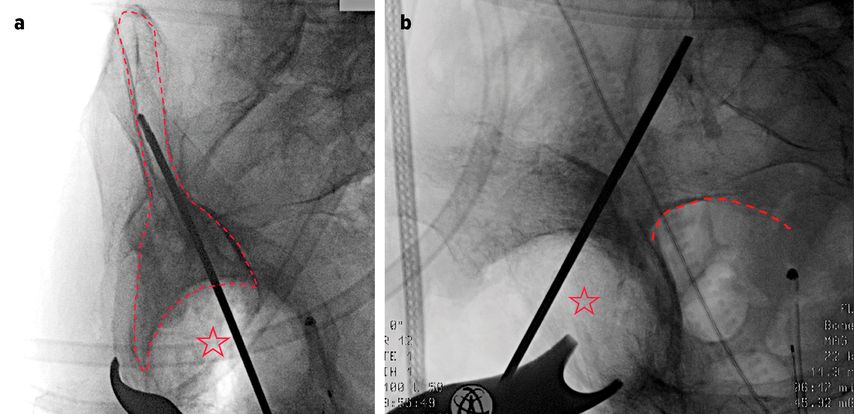

Hochbetagte Patientinnen und Patienten können in der Regel nicht mobilisiert werden, ohne die betroffene Extremität voll zu belasten. Die Ursachen hierfür können dabei sowohl körperlicher als auch kognitiver Natur sein. In diesen Fällen gewinnt die primäre endoprothetische Versorgung mit Rekonstruktionspfanne an Bedeutung (Replace-in-situ-Prinzip). Diese gewährleistet in Kombination mit der zentralen Ileumschraube eine sofortige stabile Primärverankerung der Hüftpfanne auch bei komplexen Frakturmustern und ermöglicht somit eine frühe Vollbelastung sowie Remobilisation. Ein Beispiel einer solchen Rekonstruktionspfanne stellt die Mutars® PRS (Pelvic Revision Shell) dar. Die zementfrei implantierte Rekonstruktionsschale von Implantcast zeigt Abbildung 1.